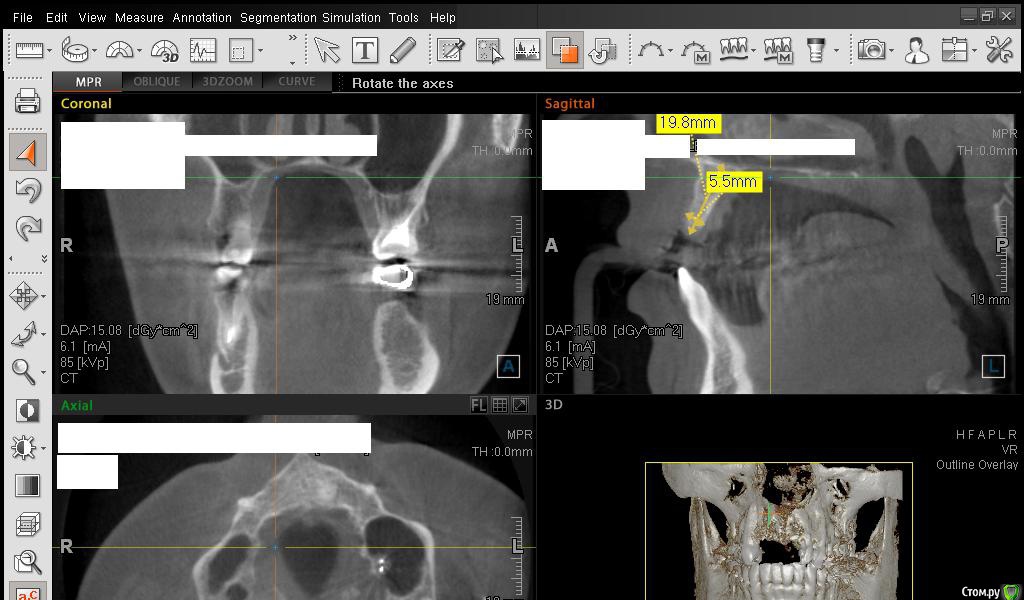

SDC Опубликовано 1 марта, 2015 Поделиться Опубликовано 1 марта, 2015 Сестричка, в левом верхнем углу КТ есть инструмент, обозначен, как линейка.С помощью ее необходимо провести замеры альвеолярного отростка на КТ вертикально и горизонтально.Для увеличения объема десны используются различные трансплантаты, но пока лучше аутотрансплантата (собственной десны с неба) ничего нет. Ссылка на комментарий

Сестричка Опубликовано 2 марта, 2015 Автор Поделиться Опубликовано 2 марта, 2015 Сделала замеры, надеюсь правильно? Старалась измерить наиболее уязвимые и тонкие места. Изначально планировались размеры имплантов 3 мм на 11 мм длиной. Смогут ли они туда встать? Ссылка на комментарий

SDC Опубликовано 2 марта, 2015 Поделиться Опубликовано 2 марта, 2015 Интересны размеры беззубого альвеолярного отростка на самой вершине его или рядом с вершиной на расстоянии 1 мм. от нее в проекции будущего местоположения имплантатов.Желательно размеры проводить рядом с объектом (как в черчении)По-моему, диаметр 3 мм. подходит для имплантации без костной пластики, но без трансплантации десны, одномоментно с имплантацией, не обойтись. 1 Ссылка на комментарий

Сестричка Опубликовано 2 марта, 2015 Автор Поделиться Опубликовано 2 марта, 2015 Интересны размеры беззубого альвеолярного отростка на самой вершине его или рядом с вершиной на расстоянии 1 мм. от нее в проекции будущего местоположения имплантатов.Желательно размеры проводить рядом с объектом (как в черчении)По-моему, диаметр 3 мм. подходит для имплантации без костной пластики, но без трансплантации десны, одномоментно с имплантацией, не обойтись.Простите безграмотную, совсем не понимаю что это за отросток и где он находится(( А размеры программа автоматически куда-то уводит, я их хотела поставить как надо, не получается. Про десну понятно, что надо все сразу делать, хирург говорил, у меня дефецит десны и келлоидные шрамы от резекций. Поэтому и предлагал материал для увеличения объема десны, но я конечно тоже больше хотела бы, чтоб взяли с неба. Ссылка на комментарий